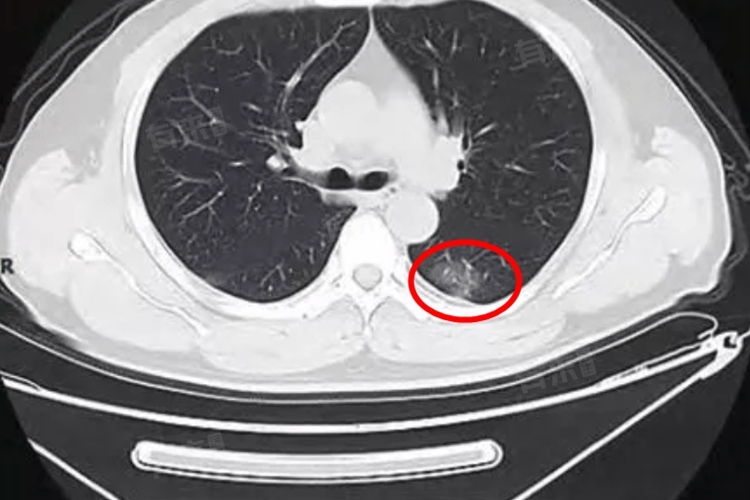

肺部磨玻璃灶是在胸部影像学检查中发现的一种表现,严重程度需要综合多方面因素判断,如果是肺炎、局部出血等导致的,没有明显不适,通常不严重,但如果是弥漫存在,或者出现恶变,通常比较严重。

- 对于早期肺癌,尤其是肺腺癌,也可能以磨玻璃灶为表现。这种情况十分严重,需要高度重视。早期肺癌的磨玻璃灶可能具有一些特征,如边界不清、有分叶、有空泡征等。需要通过进一步的检查,如病理活检、肿瘤标志物检测等明确诊断,并制定相应的治疗方案,如手术、放疗、化疗等。